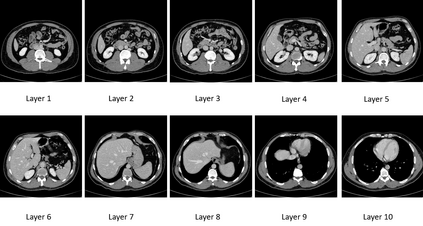

In many clinical settings, the use of both Computed Tomography (CT) and Magnetic Resonance (MRI) is necessary to pursue a thorough understanding of the patient's anatomy and to plan a suitable therapeutical strategy; this is often the case in MRI-based radiotherapy, where CT is always necessary to prepare the dose delivery, as it provides the essential information about the radiation absorption properties of the tissues. Sometimes, MRI is preferred to contour the target volumes. However, this approach is often not the most efficient, as it is more expensive, time-consuming and, most importantly, stressful for the patients. To overcome this issue, in this work, we analyse the capabilities of different configurations of Deep Learning models to generate synthetic CT scans from MRI, leveraging the power of Generative Adversarial Networks (GANs) and, in particular, the CycleGAN architecture, capable of working in an unsupervised manner and without paired images, which were not available. Several CycleGAN models were trained unsupervised to generate CT scans from different MRI modalities with and without contrast agents. To overcome the problem of not having a ground truth, distribution-based metrics were used to assess the model's performance quantitatively, together with a qualitative evaluation where physicians were asked to differentiate between real and synthetic images to understand how realistic the generated images were. The results show how, depending on the input modalities, the models can have very different performances; however, models with the best quantitative results, according to the distribution-based metrics used, can generate very difficult images to distinguish from the real ones, even for physicians, demonstrating the approach's potential.